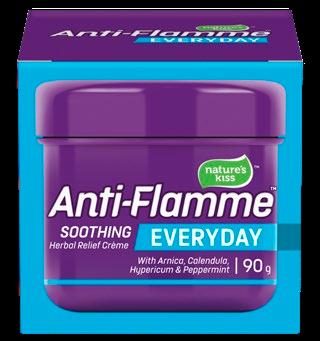

the power of Arnica oil, Calendula oil, Hypericum oil and Peppermint oil to soothe muscles. Endeavour Consumer Health, Auckland. $1899 each Anti-Flamme Crème 90g Extra | Joints | Everyday Natural restorative oils to care for your family